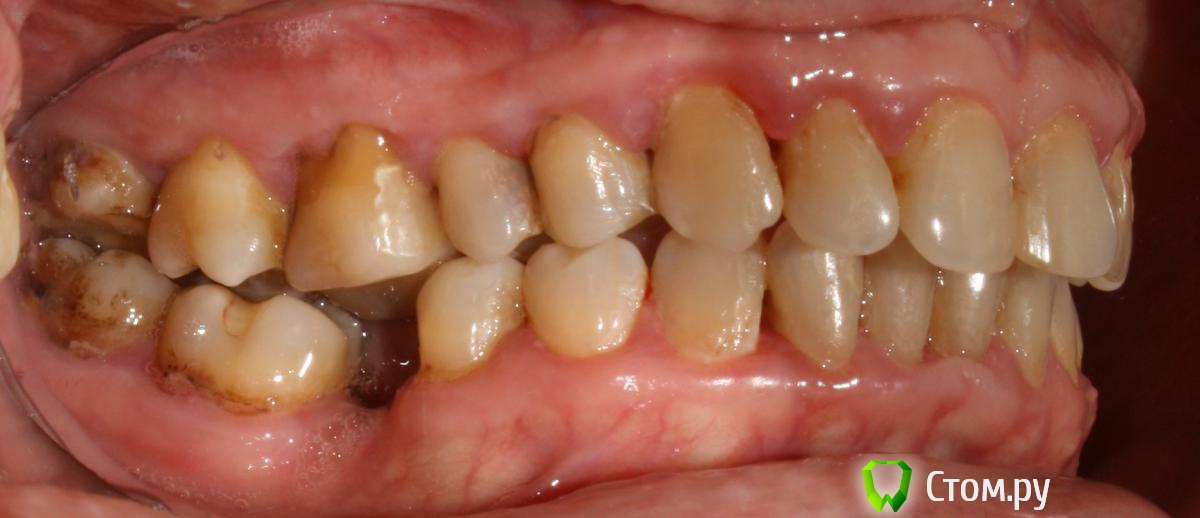

artem29 Опубликовано 12 декабря, 2013 Поделиться Опубликовано 12 декабря, 2013 всем привет!!! Я хирург. В клинике планируется работа с микровинтами. Пациентка брекетсистему "носить" не планирует (остановились на локальном решении задач) Задача: Ортопеду необходимо освободить место для будущих искусственных зубов 1.6 и 3.6. Для этого пациентка (50 лет), отправляется на консультацию к ортодонту для решения вопроса у дистализации зубов 1.7 и 3.7. В данном клиническом случае по хирургическим показаниям зубы мудрости планировались на удаление, сейчас добавились и ортодонтические, как я понимаю для дистализации 1.7 и 3.7 надо удалить 1.8 и 3.8. Ортодонт на микровинтах не работала, но мотивация есть. С ортодонтом видемся редко, у нас в клинике только консультативны прием, обсудить что-то вместе крайне редко получается (тем более провести совместную консультацию), меня как хирурга ортопед попросил посмотреть снимки, определить свой (хирургический объем работы). Изучив информацию (литературу и форумы) я пришел к такому варианту действий,чтобы дистализировать 1.7 необходимо удалить 1.8 установить микровинт вестибулярно между корнями 1.4 и 1.3 (т.к. там больше места чем между 1.5 и 1.4) к 1.7 фиксировать брекет-замок, между ними установить пружину, зуб 1.7 дистализируется. для дистализации 3.7 необходимо удалить 3.8, оценить состояние костной ткани, возможно установить микровинт дистально одномоментно с удалением 3.8 если межокклюзионной высоты для головки микровинта будет достаточно. Вторым путем (при отсутствии состоятельной костной опоры в момент удаления 3.8 является установка микровинта между корнями зубов 3.4 и 3.5, брекет на зуба 3.7 + пружина. есть ещё один вариант. удалить 1.8 и 3.8, дождаться пока пройдет формирование костной ткани (сделать КТ через 3 месяца) установить микровинты в уже сформированную кость Вопросы: 1. кто определяет место установки микровинтов, ортодонт или хирург? 2. если изначально определяет место установки винтов хирург, то какие зоны необходимо в данной случае взять за костные опоры (куда ставить установить микровинты) к какие ортодонтические конструкции будут? 3. оптимально ли в данной ситуации дистализировать с помощью микровинтов, или возможны другие варианты Ссылка на комментарий

M@estro Опубликовано 12 декабря, 2013 Поделиться Опубликовано 12 декабря, 2013 Интрузию 4.6 и 2.6 я просить бы не стал. (а 2.6 вообще под вопросом на выход). Думаю, дистализацию в первом квадранте можно выполнить "пружинкой" ,оттолкнувшись от премоляров,хотя утверждать не берусь. P.s. Гигиена - кошмар. Ссылка на комментарий